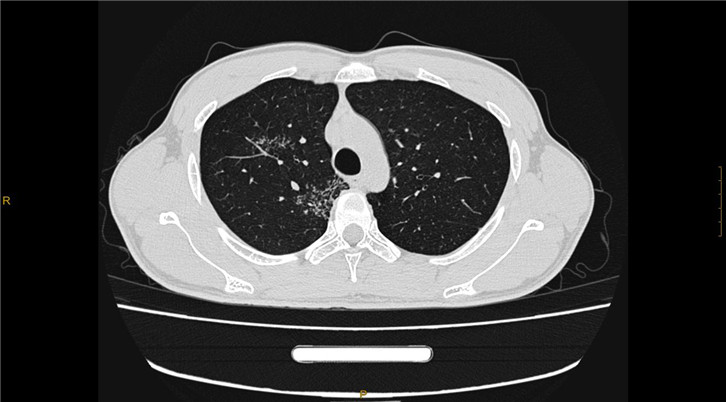

·0.275mm ultra-thin layer scanning can clearly show the fine structures in the human body, such as inner ear and small pulmonary nodules

Clinical Gallery